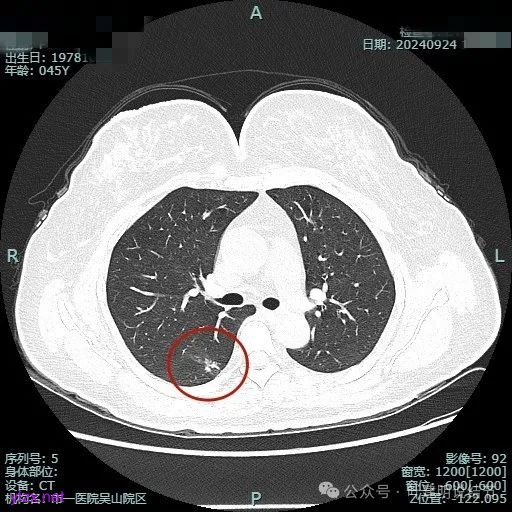

我们先来看2024年9月时的影像:

病灶1:

右下背段混合密度病灶,边上不太清爽,有片状淡磨玻璃影,实性部分密度较高。

感觉病灶有点晕征似的,表面不平,灶内不太致密。

有小血管进入,似有晕征。

离胸膜近但牵拉不明显,病灶边缘有细毛刺,较短且不太锐利。

边缘少许磨玻璃成分,血管进入明显。

瘤肺边界稍显不清。